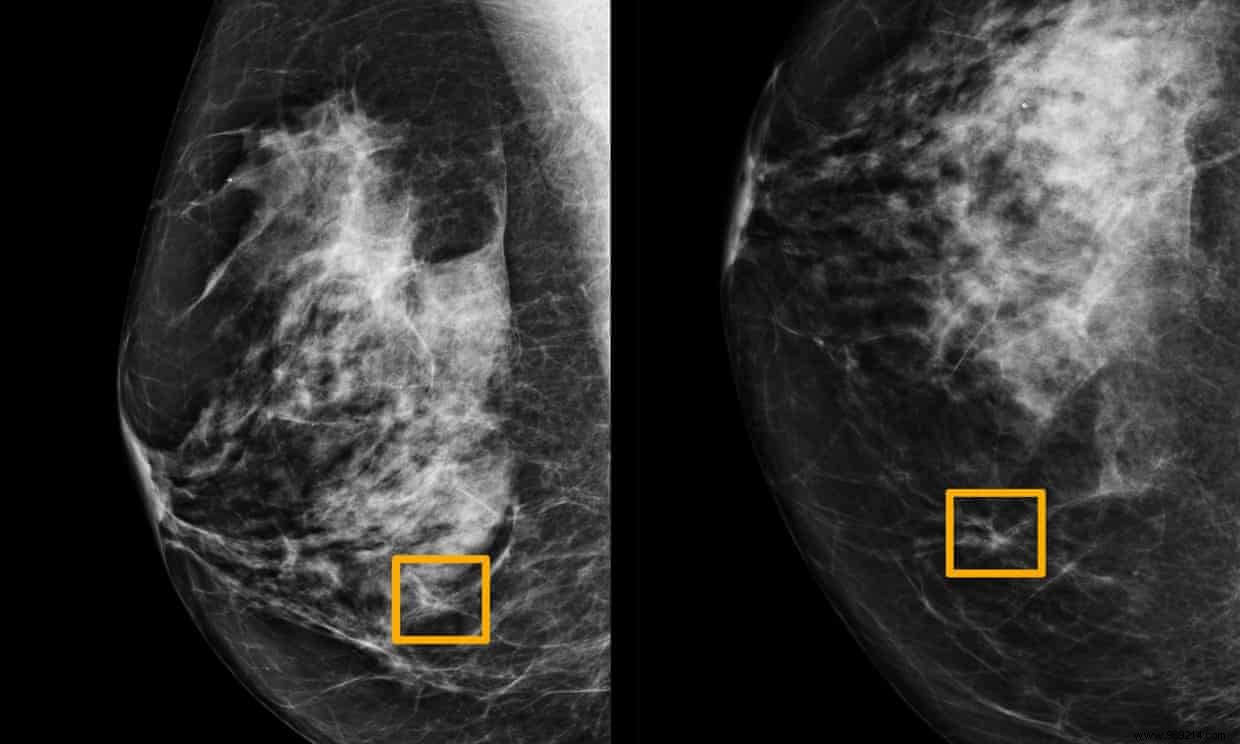

A groundbreaking study shows a new AI system surpassing radiologists in identifying breast cancer from mammograms.

Researchers worldwide have spent years refining AI to boost mammography accuracy. Google Health's advanced system, trained on 91,000 mammograms, was rigorously tested on two datasets totaling 28,000 more scans—one from U.S. women and one from the U.K.

In the U.S. dataset, the AI reduced 5.7% fewer false positives and 9.4% fewer false negatives than physicians, catching more cancers they overlooked.

For the U.K. data, reviewed by two radiologists to minimize human error, the AI still excelled with 1.2% fewer false positives and 2.7% fewer false negatives.

In a head-to-head challenge, six U.S. radiologists analyzed 500 random mammograms against the AI. The system spotted cancers missed by all experts, though it missed one case they caught—highlighting its impressive, though not flawless, performance.